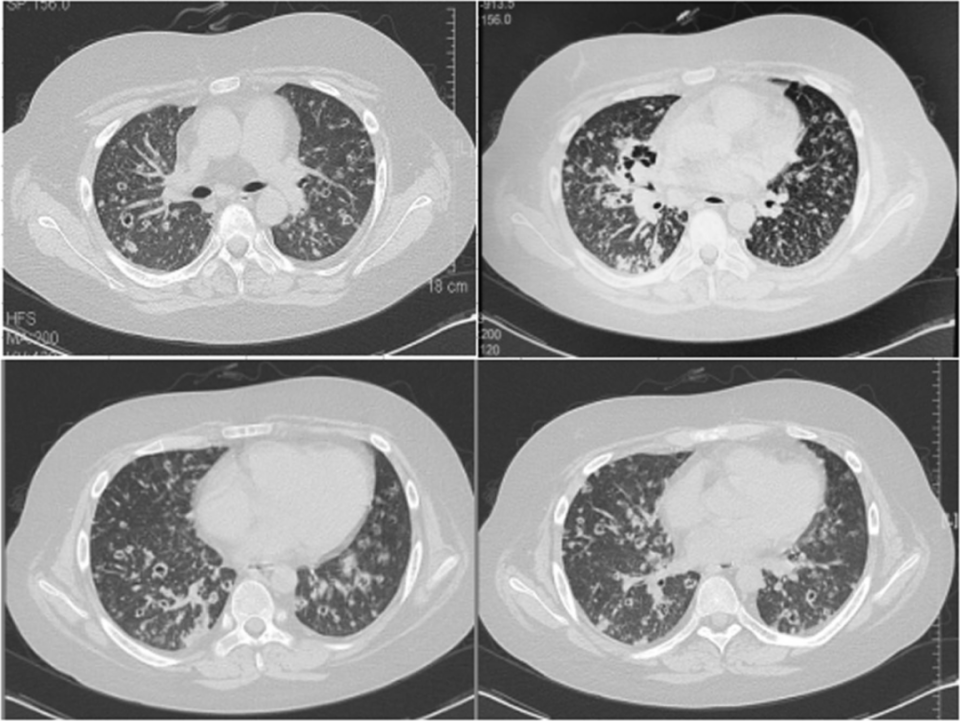

由于细菌含量高且传播范围广,因此给予两性霉素B脂质体(安必素®)60 mg qd(1 mg·kg-1·d-1)补充治疗,3天后患者发烧终于消失。经过10周的治疗,患者的症状消失了,随访的CT扫描显示双肺病变吸收明显,右中叶空洞病变明显改善(图3)。

图片图3. 治疗10周后,重复胸部CT显示病变吸收明显[1]

因病情稳定,患者被转移至当地社区医院继续治疗。出院5个月后,通过电话获取了相关的患者随访信息。数据显示,在随后用氟康唑治疗后,CSF标本显示新生隐球菌呈阴性,胸部CT图像显示隐球菌病变明显吸收且空腔闭合。